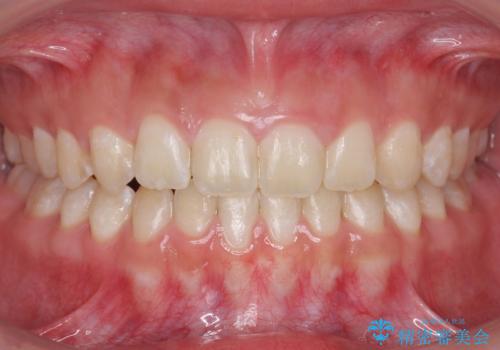

[ 前歯のねじれ・がたつき ] マウスピース矯正

![[ 前歯のねじれ・がたつき ] マウスピース矯正の症例 治療前](https://seimitsushinbi.jp/wp/wp-content/uploads/2024/02/4007c6479f6bce11863dcdd32ed5e39b-500x350.jpg?v=1708502552)

![[ 前歯のねじれ・がたつき ] マウスピース矯正の症例 治療後](https://seimitsushinbi.jp/wp/wp-content/uploads/2024/02/e7a01485e4f4dd0da04705fde4cc34cc-500x350.jpg?v=1708502585)

インビザライン モニター治療 前歯のねじれをまっすぐに